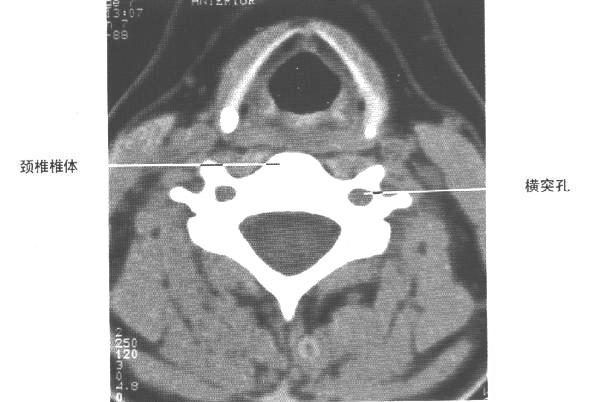

颈椎椎体层面